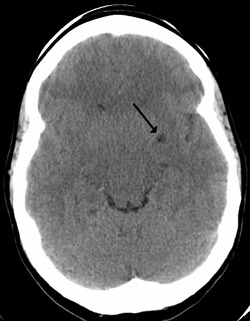

Perivascular space is depicted in the inset box.

Perivascular spaces are distinguished on an MRI by several key features. The spaces appear as distinct round or oval entities with a signal intensity visually equivalent to that of cerebrospinal fluid in the subarachnoid space.[7][14][15] In addition, a perivascular space has no mass effect and is located along the blood vessel around which it forms.[14]